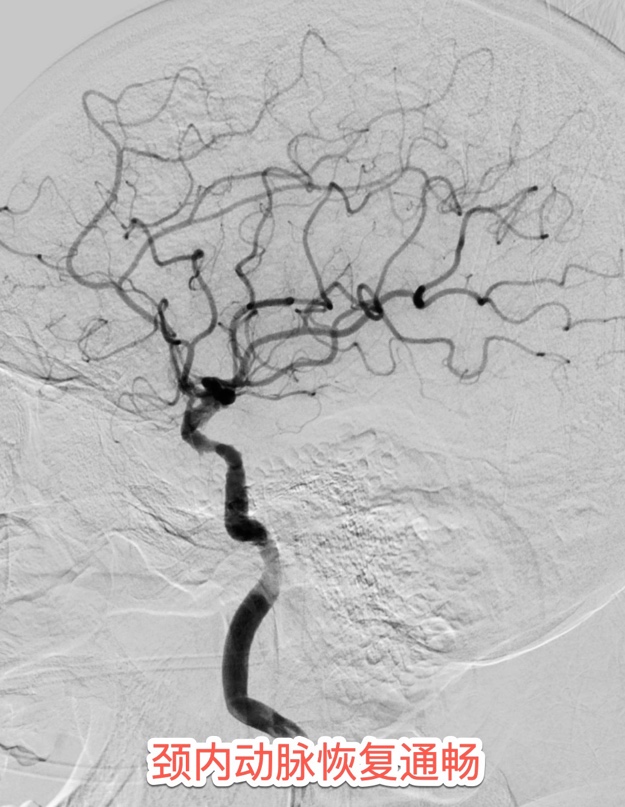

患者住院期间的心电图提示心房颤动病史,发病紧急,没有明显的前驱症状,考虑房颤栓子脱落所致的脑动脉栓塞。介入团队采用最新一代球囊Guilding导管,充盈球囊时可以阻断近段血流,避免血栓逃逸,同时经导管抽吸血栓,可以明显的提高血栓抽吸效率。最终在此先进的医疗技术下精准"抓捕"出大量团块状的暗红色血栓。

术后第二天查房,苏醒后的白先生突然清晰说出"谢谢医生",右侧肢体也恢复了正常肌力。病房内洋溢着劫后余生的喜悦及大功告成后的欣慰,这声清晰可鉴的“谢谢成为这场大脑保卫战的最美捷报。术后48小时复查显示,NIHSS神经功能评分从入院时的17分(重度缺损)降至0分,磁共振DWI序列未见新鲜梗死灶,实现临床与影像学的"双重治愈"。据介入医学科王宁副主任医师介绍,大血管闭塞性脑卒中每延迟30分钟治疗,良好预后概率下降12%。此次病人的抢救,医院的"院内卒中应急体系"发挥关键作用,为后续治疗赢得宝贵时间。"